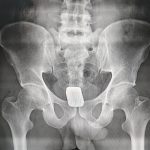

পরবর্তীতে তাকে শিবগঞ্জ উপজেলা স্বাস্থ্য কমপ্লেক্সে নেওয়া হয়। সেখানে থানা পুলিশের উপস্থিতিতে এক্স-রে পরীক্ষার মাধ্যমে তার পায়ুপথে লুকানো দুটি স্বর্ণের বার উদ্ধার করা হয়।

চাঁপাইনবাবগঞ্জ স্বর্ণ জুয়েলারি সমিতি পরীক্ষা করে উদ্ধারকৃত স্বর্ণের সত্যতা নিশ্চিত করেছে। স্বর্ণের মোট ওজন ২৩১.৮১ গ্রাম, যার বাজারমূল্য প্রায় ৫৩ লাখ ৯৪ হাজার ৬০০ টাকা।